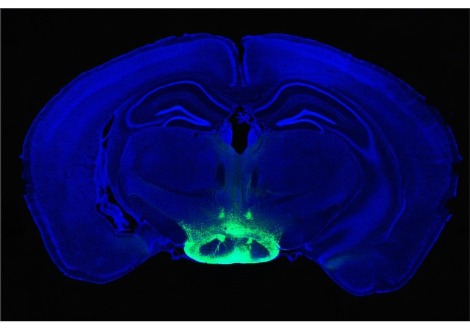

توصلت دراسة جديدة وكبيرة إلى أن الأمريكيين السود والأسبان والآسيويين معرضون بشكل متزايد للإصابة بالخرف مع تقدمهم في العمر لأسباب غير مفهومة تمامًا .

وجدت الدراسة ، التي شملت ما يقرب من 1.9 مليون من قدامى المحاربين في الولايات المتحدة ، أنه مقارنة بنظرائهم البيض ، كان المحاربون القدامى السود أكثر عرضة بنسبة 54 ٪ للإصابة بالخرف على مدى عقد من الزمان . تضاعف هذا الخطر تقريبًا بين قدامى المحاربين من أصل إسباني ، الذين يعانون من أعلى معدل للخرف بين المجموعات العرقية والإثنية .

ووجدت أن قدامى المحاربين من أصل آسيوي لديهم مخاطر أعلى إلى حد ما (20 ٪) من أقرانهم البيض. في غضون ذلك ، كان لدى الأمريكيين الأصليين مخاطر على قدم المساواة مع قدامى المحاربين البيض .

على مدى 10 سنوات ، تم تشخيص إصابة 13٪ بالخرف . كان المعدل الأعلى بين المحاربين القدامى  من أصل إسباني ، حوالي 21 حالة لكل 1000 كل عام ، يليهم المشاركون السود ، بمعدل 19 لكل 1000 . كان للمحاربين البيض أقل معدل (11.5 لكل 1000 كل عام) ، بينما انخفض عند المحاربين القدامى الآسيويين والأمريكيين الأصليين في مكان ما بين (ما يزيد قليلاً عن 12 و 14 حالة ، على التوالي ، لكل 1000) .

بمجرد أن يضع الباحثون في الاعتبار عوامل أخرى - مثل ما إذا كان المحاربون القدامى لديهم تاريخ من ارتفاع ضغط الدم أو السكري أو السكتة الدماغية أو إصابة الدماغ - كان العرق لا يزال عامل خطر مستقل للخرف . كان هذا صحيحًا بشكل خاص بالنسبة لقدامى المحاربين من أصل إسباني والسود .